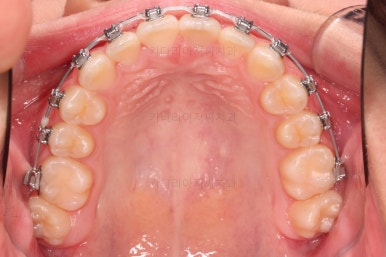

✅ 악궁 확장

악궁확장 내용이 나올 때면 매번 말씀 드리는 내용이 있습니다.

치열이 삐뚤었다고 공간확보 목적으로 악궁확장을 하는 건 아니다.

아래와 위의 턱뼈의 크기 부조화가 있을 때 위턱을 넓혀주는 것이 악궁확장이며, 저희 부산청소년교정치과 키다리아저씨치과에서는 정교한 3차원 CT분석을 이용해서 골격의 크기를 비교해서 꼭 필요한 경우에 악궁확장을 해주게 됩니다.

당연히 확장을 하면 부가적으로 공간확보가 일정 부분 더 잘된다는 효과도 있지만 공간확보를 위해서 턱뼈의 크기가 조화로운데도 불구하고 악궁확장을 한다면 또 다른 좋지 못한 결과가 생길 수 있어서 매우 조심스러운 평가가 선행되어야 합니다.

이번 환자분은 악궁확장이 필요한 케이스였으며, 청소년이었기 때문에 별도의 미니스크류 없이 일반 확장장치를 이용했습니다.

악궁확장부터 시행합니다.

확장이 잘 되어 앞니 사이에 틈새도 잘 벌어진 것이 확인되고요.

적절한 시기에 시차를 두고 순차적으로 브라켓을 부착합니다.